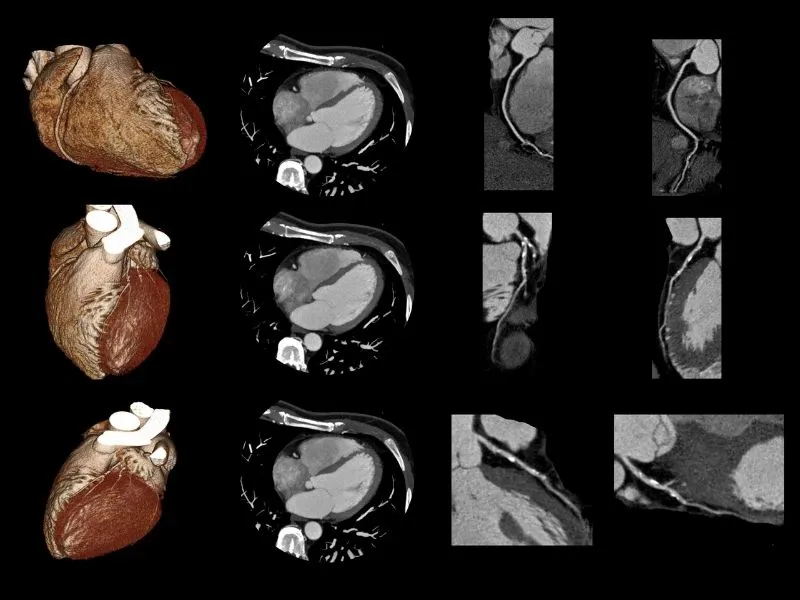

O escore de cálcio coronariano (CAC) é uma medida quantitativa da carga de aterosclerose calcificada nas artérias coronárias — obtida por meio de tomografia computadorizada sem contraste, de baixa dose de radiação, com duração de aproximadamente 10 a 15 minutos. Não exige jejum, não utiliza contraste iodado e não é invasivo.

O método mais utilizado para quantificação é o Escore de Agatston — padrão de referência internacional, que calcula a pontuação a partir da densidade e da área de cada depósito calcificado detectado nas artérias coronárias (descendente anterior, circunflexa, coronária direita e tronco da coronária esquerda). O resultado é expresso em Unidades Agatston (UA).